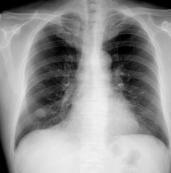

肺错构瘤是指包含肺的所有正常组织成分, 但构成成分数量异常、排列异常或分化程度异常等所形成的肿瘤样畸形。肺错构瘤不是真性肿瘤(也有研究者主张其为真正的肿瘤),而是胚叶的发育异常,起源于肺内正常组织,主要为软骨、纤维结缔及脂肪组织等形成的肿瘤样病变。因其性质及影像学特征近似良性肿瘤,故列为良性肿瘤范围内。根据其成份分为软骨型及纤维型。根据部位分中央型和周围型 。发生于气管、叶支气管粘膜下称中央型。发生于肺内的称周围型,周围型多位于胸膜下。